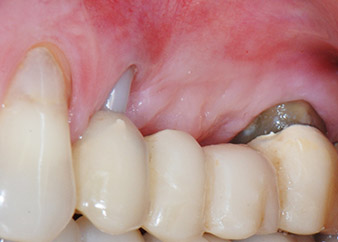

Фигури 17 и 18 показват клиничния резултат два месеца след операцията. Зъб 24 показва намалена подвижност на Милър клас 1 и меките тъкани не са възпалени. Сондирането е избегнато на този етап, за да се избегне повторно възпаление и нарушение на епителната надстройка. Планиран е контролен преглед за повторно отваряне и поставяне на оздравителни абатмънти, шест месеца след поставяне на имплантите.

На прегледа след два месеца, мобилността на останалия "дентален елемент" 24 вече е намалена от Милър 2 на Милър 1. Захващането на меките тъкани е на нивото на съседния зъб 23. Освен това, няма ендодонтски или периодонтални симптоми, така, че прогнозата трябва да се коригира.